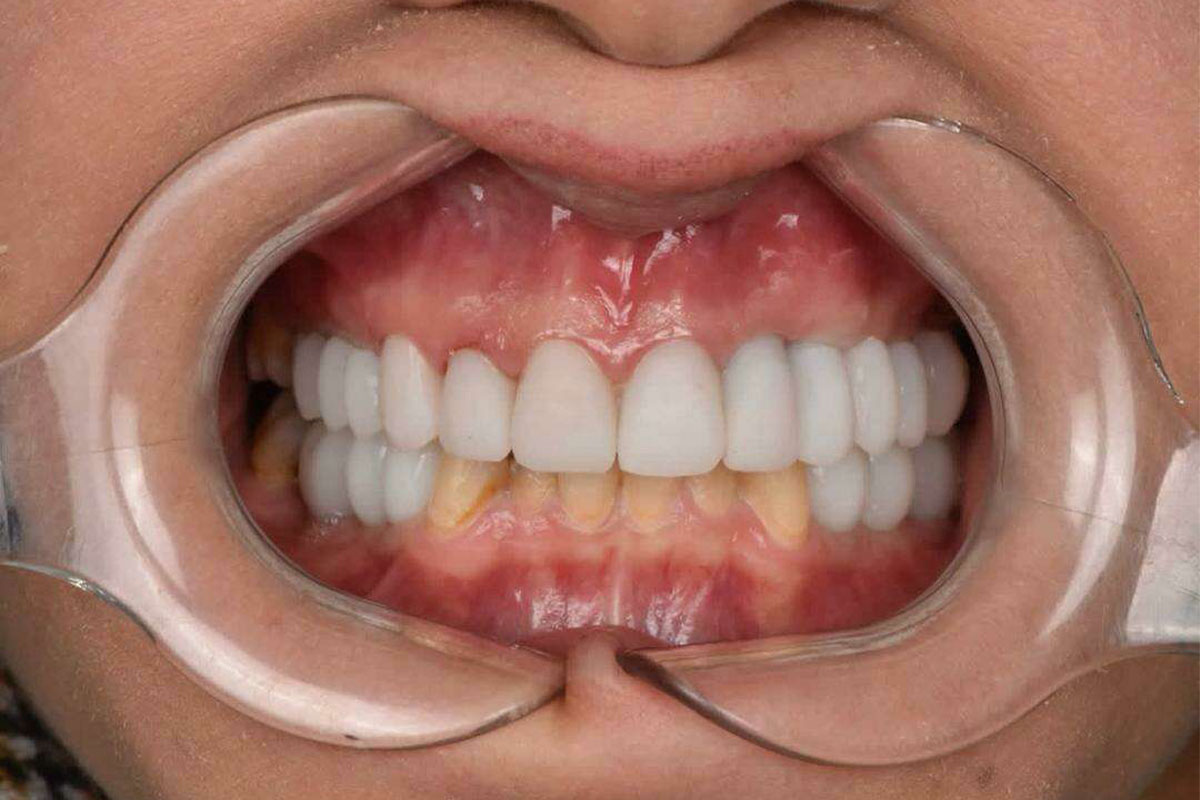

نمونه کارهای عصب کشی دندان